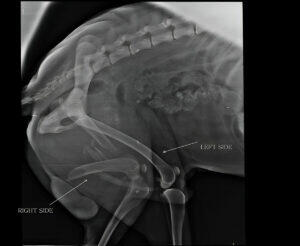

Gun dogs happen to have a lot of knee and joint injuries due to their hunting and working nature. The reports suggest that working and gun dogs are likely to be 60% more prone to have a cruciate injury. However, training gun dogs can reduce these medical problems.

Cruciate Ligament Rupture

This is a common injury that gun dogs happen to experience due to their work. Musculoskeletal injuries are especially common in larger breeds, resulting in knee joint instability.

The treatment of this rupture may vary. It could start from conservative management, such as rest physiotherapy, to surgical interventions like tibial plateau leveling osteotomy (TPLO). The intensity of the rupture plays a crucial role in the final treatment option.

Hip Dysplasia

The next condition is Hip Dysplasia a hereditary condition that affects the hip joint, often leading to pain. This also causes lameness in dogs, eventually leading them to have arthritis.

Managing Hip Dysplasia

Hip dysplasia is tried to manage well before going for treatment, which could be in severe cases. The veterinarians can train the parents to consider the following.

Moreover, severe cases may call for surgical intervention.

Elbow Dysplasia

Elbow dysplasia can indicate the development of abnormalities affecting the elbow joint, causing pain and lameness.

Treatment

The treatment of elbow dysplasia ranges from conservative management to surgical procedures depending on the intensity of the abnormalities developed.

It is important to mention here that these musculoskeletal injuries often make the gun dogs have unspecific lameness. They could feel sluggish and limp, showing no interest in running or their hunting activities. Therefore, gun dog nutrition is crucial to monitor and care for the do to excel in his work.